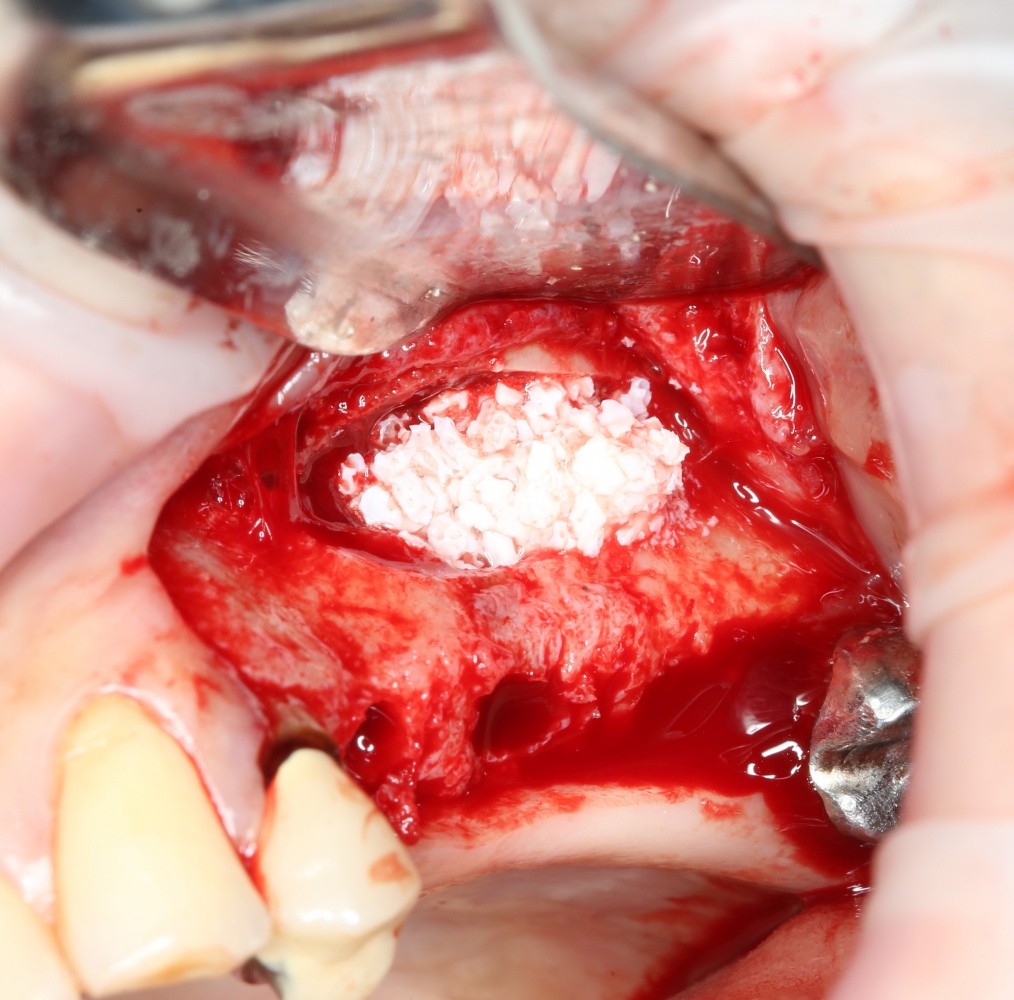

Если ты читал мои предыдущие публикации, посвященные остеопластике, то наверняка знаешь, что костное ложе перед фиксацией графта (любого графта) требует некоторой подготовки. В основном она заключается в полном или частичном удалении кортикального слоя и, применительно к АТККФ — адаптации не только блока под ложе, но и ложа под пересаживаемый костный блок. Подробности здесь>>

Ежу понятно, что к необходимости этих манипуляций мы пришли не сразу. А тогда был 2013 год… и у меня были мысли, что подготовка костного ложа нужна не всегда и не всем. Здесь я понадеялся на размер костного дефекта и большую площадь контакта между костным аутотрансплантатом и принимающим ложем. Конечно, сейчас я сделал бы немного по-другому.

Я зафиксировал костный блок практически без адаптации на несколько винтов. Обрати внимание, что винты находятся в зоне, где не планируется установка имплантатов. Фиксация должна быть надежной, поскольку мне еще предстояла подготовка лунок для имплантатов. Трех винтов для этого вполне достаточно.

Дальнейшая адаптация костного блока свелась к сглаживанию острых краев. После чего я приступил к подготовке лунок и установке имплантатов.